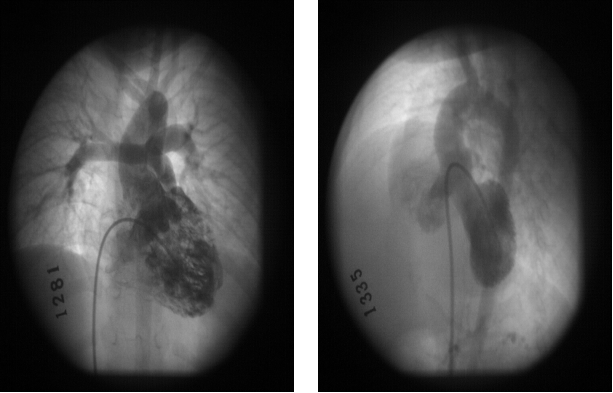

法洛四联症:心血管造影表现

一般情况下不需要心血管造影诊断法洛四联症

用于评估外周血管发育情况、体肺侧支循环、冠状动脉起源与走行等